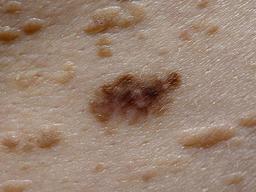

MILK10k consists of 10480 images, each representing a paired clinical close-up and dermatoscopic image for 5240 lesions. The dataset’s metadata include age (in 5-year intervals), sex, anatomic site, skin tone, diagnosis, method of ground truth establishment (histopathology or other means), and, if a dermatoscopic image of the same lesion was previously included in ISIC, its corresponding ISIC identifier. Skin tone is categorized into six levels, ranging from very dark (0) to very light (5), intentionally distinct from the Fitzpatrick skin types to avoid confusion. Most patients had skin tones in the middle ranges. Of the 5240 lesions, 95.7% were biopsied or excised, with histopathology serving as the gold standard for diagnosis. Diagnoses were mapped to both the ISIC-Dx diagnostic scheme and a simplified classification based on the ISIC2018/2019 challenge and HAM10000 diagnostic categories. The dataset includes 11 broad diagnostic categories:

- Basal cell carcinoma (bcc)

- Melanocytic nevus (nv)

- Benign keratinocytic lesion (bkl)

- Squamous cell carcinoma/keratoacanthoma (sccka)

- Melanoma (mel)

- Actinic keratosis/intraepidermal carcinoma (akiec)

- Dermatofibroma (df)

- Inflammatory and infectious conditions (inf)

- Vascular lesions and hemorrhage (vasc)

- Other benign proliferations including collision tumors (ben_oth)

- Other malignant proliferations including collision tumors (mal_oth)

Additionally, we provide the most specific ISIC-Dx diagnosis and its parent branch in the ISIC-Dx diagnostic tree. In cases where a dermatoscopic image of the same lesion was already included in the ISIC archive, its ISIC identifier is reported in the metadata. Furthermore, all images have been annotated using the MONET framework, with probabilities for the following concept term groups included in the metadata: